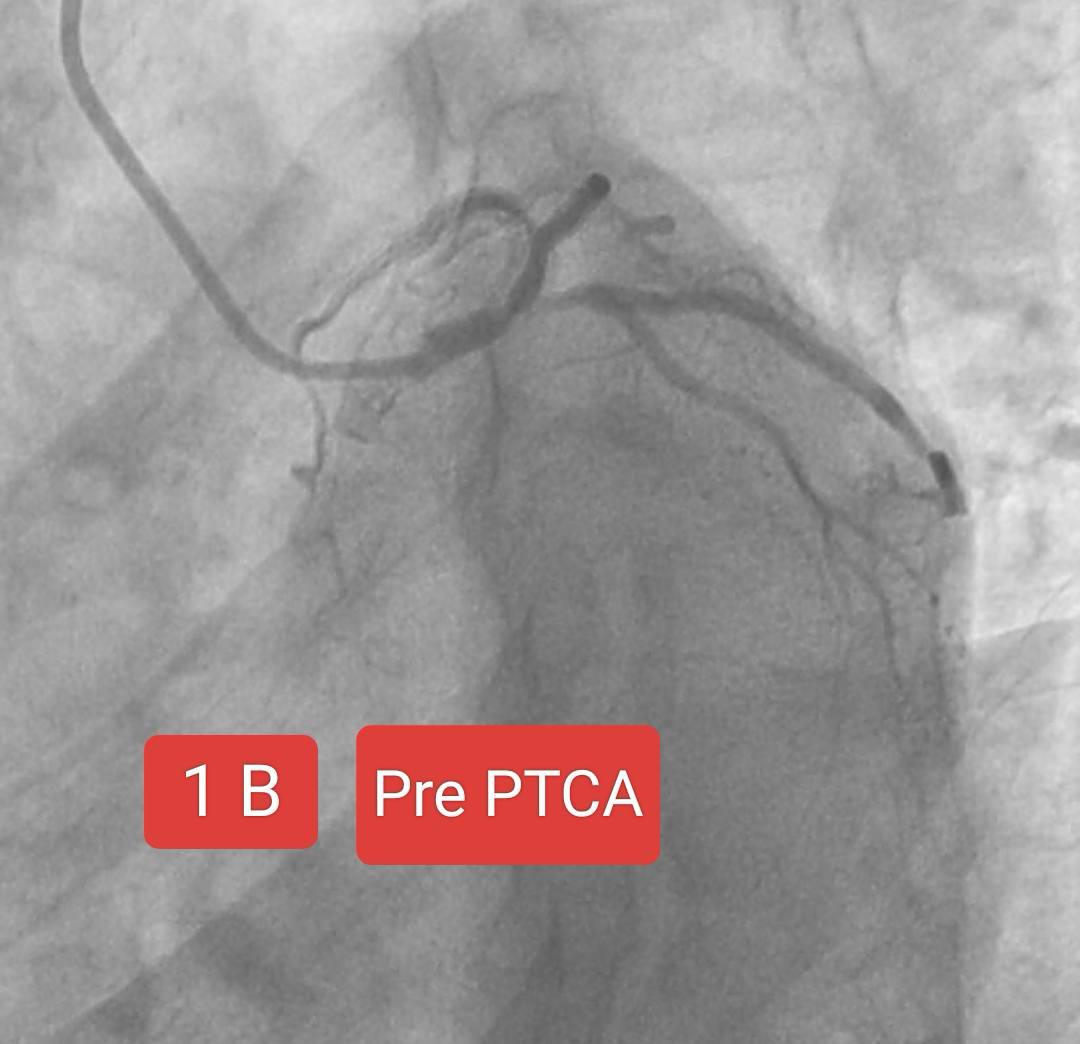

Two interesting cases of Left main stenting by mini crush technique done at Sunshine Hospital ,Bhubaneswar last month. Case 1 A 65 Years old Male Risk factors : Smoking, Hypertension Presented with Chest pain since 2 days ECG : Anterior wall STEMI ECHO : RWMA LAD Territory, LVEF 38% CAG : Left main + LAD + LCx disease PTCA done : Left main bifurcation stenting by Mini crush technique Case 1B 72 year old Male Risk factor : Smoking CAD Post PTCA status to OSTIOPROXIMAL LAD - D1 ( Bifurcation) ( 2020) Medications discontinued since 2022. ECG : aVR ST elevation ECHO : RWMA LAD Territory, LVEF : 45% CAG : Distal LMCA 95%, ostial LAD stent ISR 95% , ostial LCx 99% Patient refused CABG PTCA done : Left main bifurcation stenting by Mini crush technique Thanks to our cath lab team ( Sarfaraj Ahammed , Amit Gourav Bagh , Madhu Smita Swain , Anjan Jagannath Dash, Sanjib, Mami didi, Sameer and Raju) and Sunshine Hospital Bhubaneswar